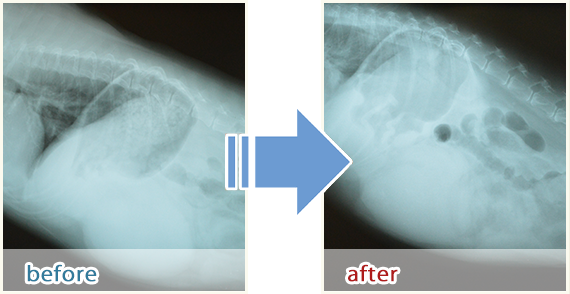

治療例【2】

口腔内にメラノーマを発症したミニチュアダックス。

メラノーマとは、口や足先など、皮膚に発生する腫瘍のことです。半導体レーザー照射後、

腫瘍が小さくなり、黒みも引きました。